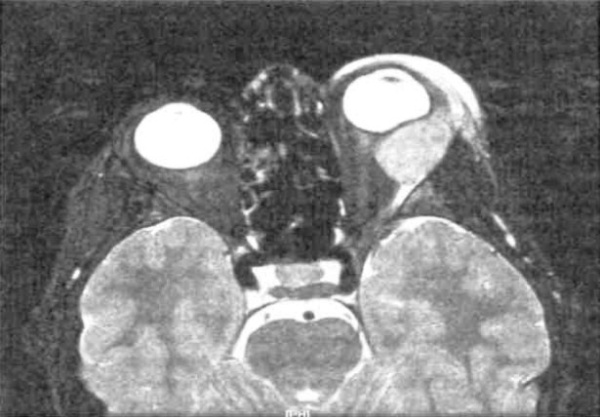

(Слева) При КТ с КУ в корональной проекции в нижней части левой глазницы определяется инфильтративное лимфопролиферативное образование, прорастающее в нижнюю глазничную щель. Отмечаются типичные гомогенность и нечеткость контуров новообразования.

(Справа) При КТ с КУ в сагиттальной проекции наблюдается дальнейшее инфильтративное распространение опухоли из задней части глазницы через нижнюю глазничную щель в крылонебную ямку. Нечетко отграниченные новообразования зачастую принадлежат к более агрессивному гистологическому типу.